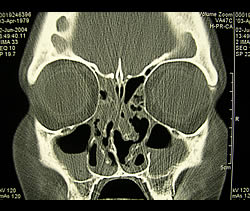

Coronal CT of Sinusitis

This computerized x-ray of the sinuses gives fine detail about soft tissue swelling, the presence of fluid, and anatomic abnormalities deep in the sinus cavities. These images are often best obtained while you lay down on your stomach with your chin down and your neck extended.